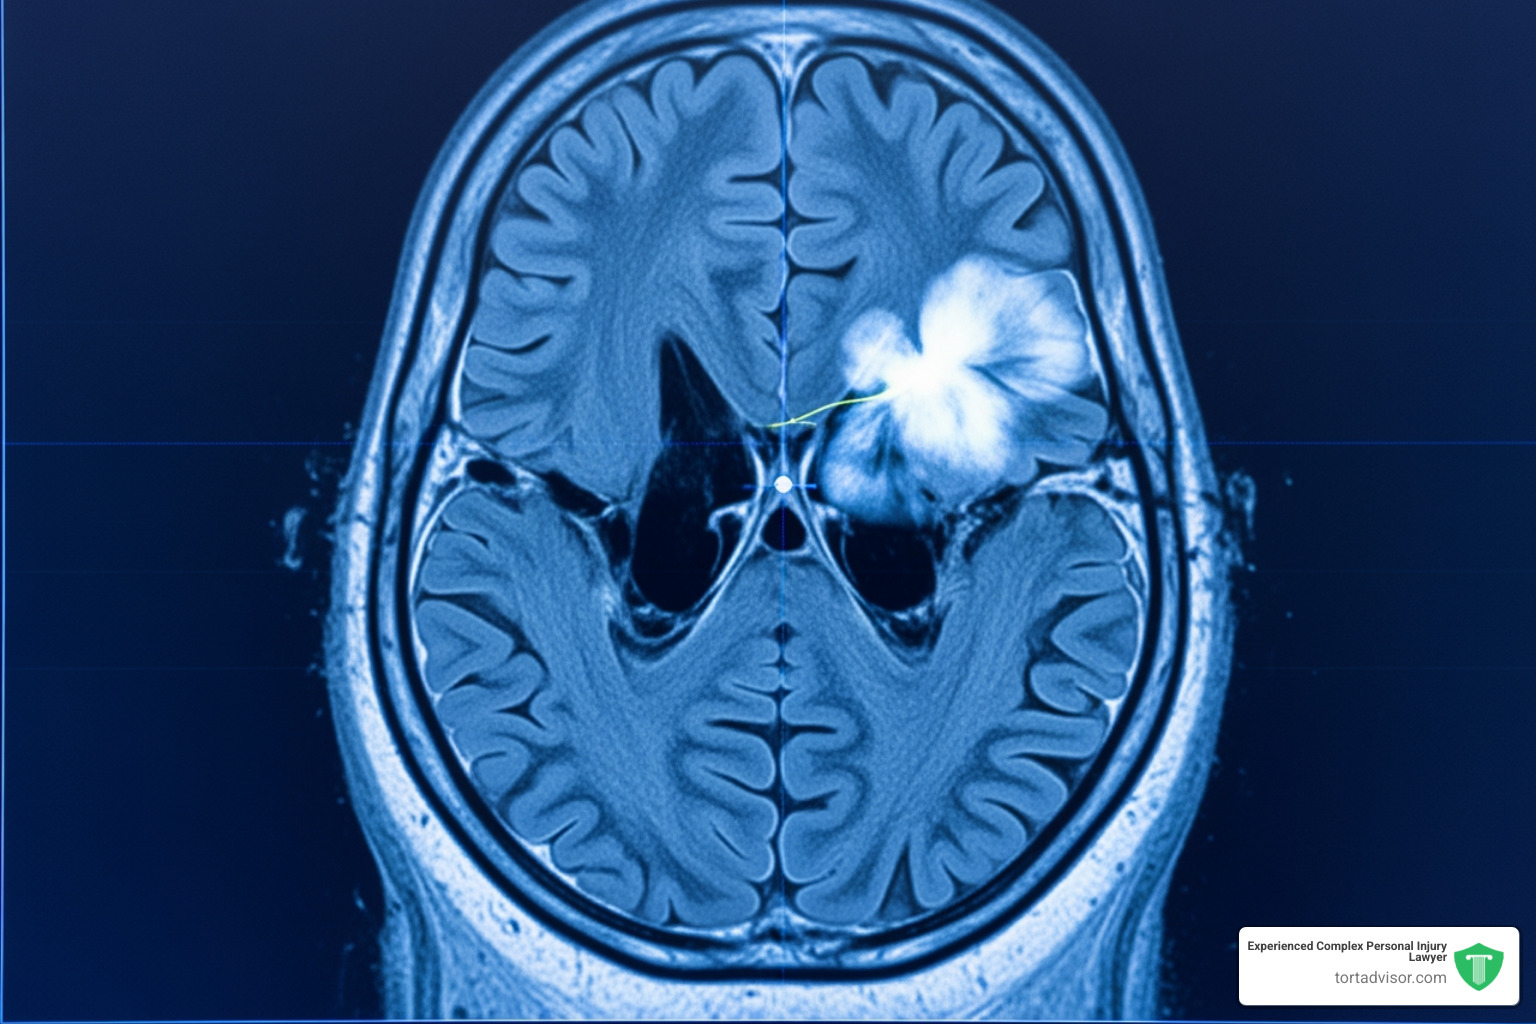

The medical condition central to these lawsuits is a meningioma, a tumor that grows in the meninges, the protective membranes covering the brain and spinal cord.

Meningiomas are the most common type of primary brain tumor. While most are technically benign (non-cancerous), they are not harmless. As a tumor grows within the skull, it presses on the brain and nerves, which can trigger severe headaches, vision loss, hearing problems, seizures, and weakness in the limbs. Some patients also experience memory issues or personality changes.

The connection involves Depo-Provera’s active ingredient, medroxyprogesterone acetate (MPA), a synthetic version of the hormone progesterone. The link is that many meningiomas are hormone-sensitive tumors. Research has shown that meningioma cells often have numerous progesterone receptors on their surface.

When synthetic progestins like MPA bind to these receptors, they can stimulate tumor growth. The biological theory is that regular, high-dose injections over several years could fuel the development or growth of these hormone-sensitive tumors. This scientific foundation is a central argument in the current depo provera lawsuit news.

A landmark study in The British Medical Journal in March 2024 significantly strengthened the scientific case against Depo-Provera. The comprehensive, peer-reviewed study found that women who used Depo-Provera for more than one year faced a 5.6-fold increased risk of developing meningiomas.

Eligibility generally depends on several factors. You must have used Depo-Provera, Depo-SubQ Provera 104, or an authorized generic version for at least one year. You also need an image-confirmed diagnosis of a meningioma brain tumor from an MRI or CT scan.